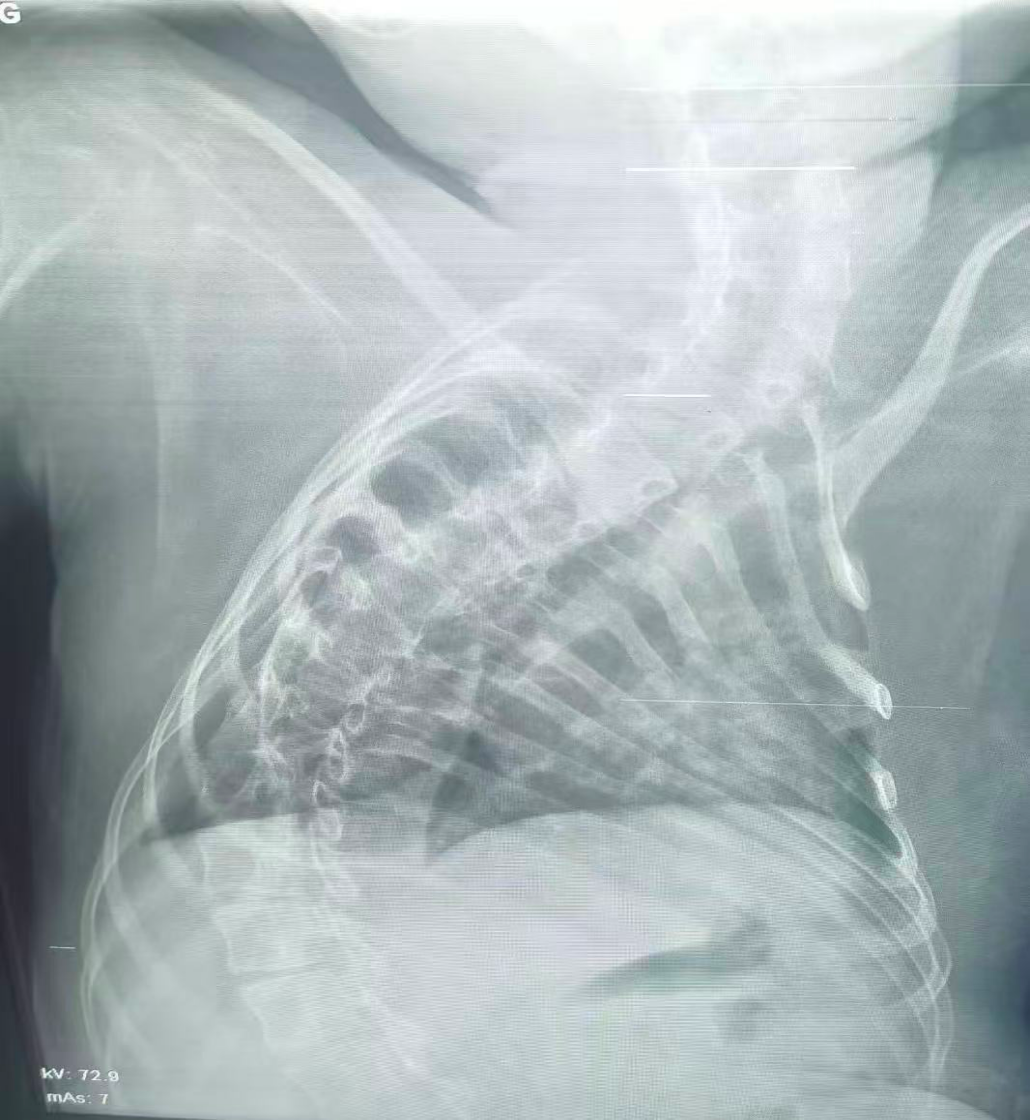

治療后

經(jīng)過(guò)團(tuán)隊(duì)的不懈努力,手術(shù)最終順利完成。術(shù)后患兒生命體征趨于平穩(wěn),氣道堵塞情況得到顯著改善,目前正在進(jìn)一步康復(fù)中。